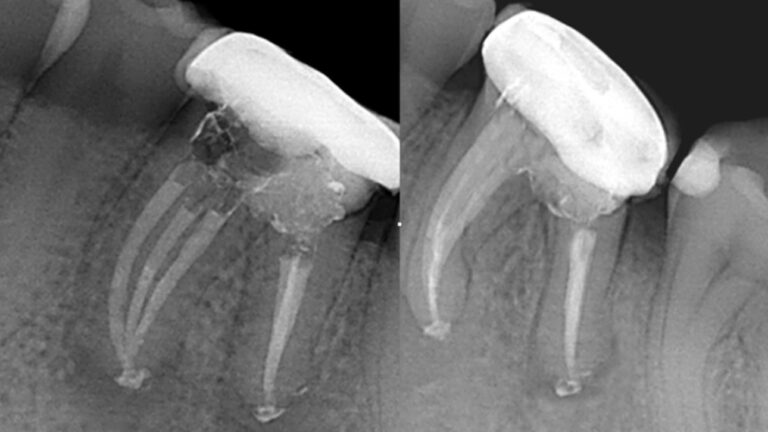

Los casos de retratamiento a menudo se complican y es por eso por lo que el retratamiento requiere…